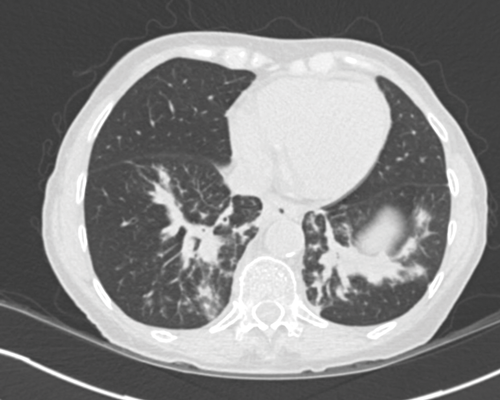

Figure 8. Axial CT shows bilateral lower lobe linear opacities with thickening

of the bronchovascular markings in keeping with bleomycin lung.

Bleomycin lung can be seen in some patients, and is typically seen as linear areas of atelectasis in the lower lobes (Figure 8). It can be subtle or more florid, and if patients are still taking bleomycin, this is stopped and they may be treated with steroids.

The radiological appearances may not improve after treatment and it is an area that the radiologist should be aware of when reporting post-treatment CT.